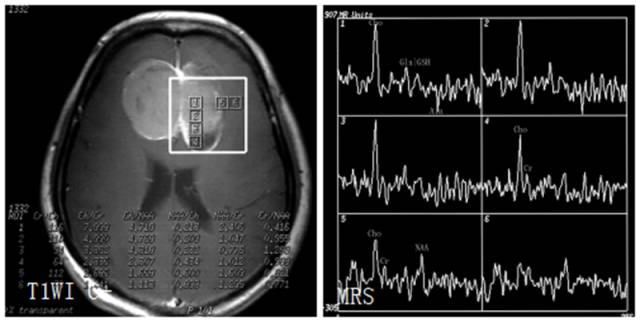

TIWI C 显示病灶增强,呈囊、实性。MRS 病灶内波谱显示Cho峰明显升高,Cr、NAA峰无或甚低,出现GHS、Gly峰。虽肿瘤呈分叶状,但囊性区(体素4)不见Lip峰,提示为囊变而非坏死,且无明显瘤周浸润,故应诊断为良性囊性脑膜瘤。